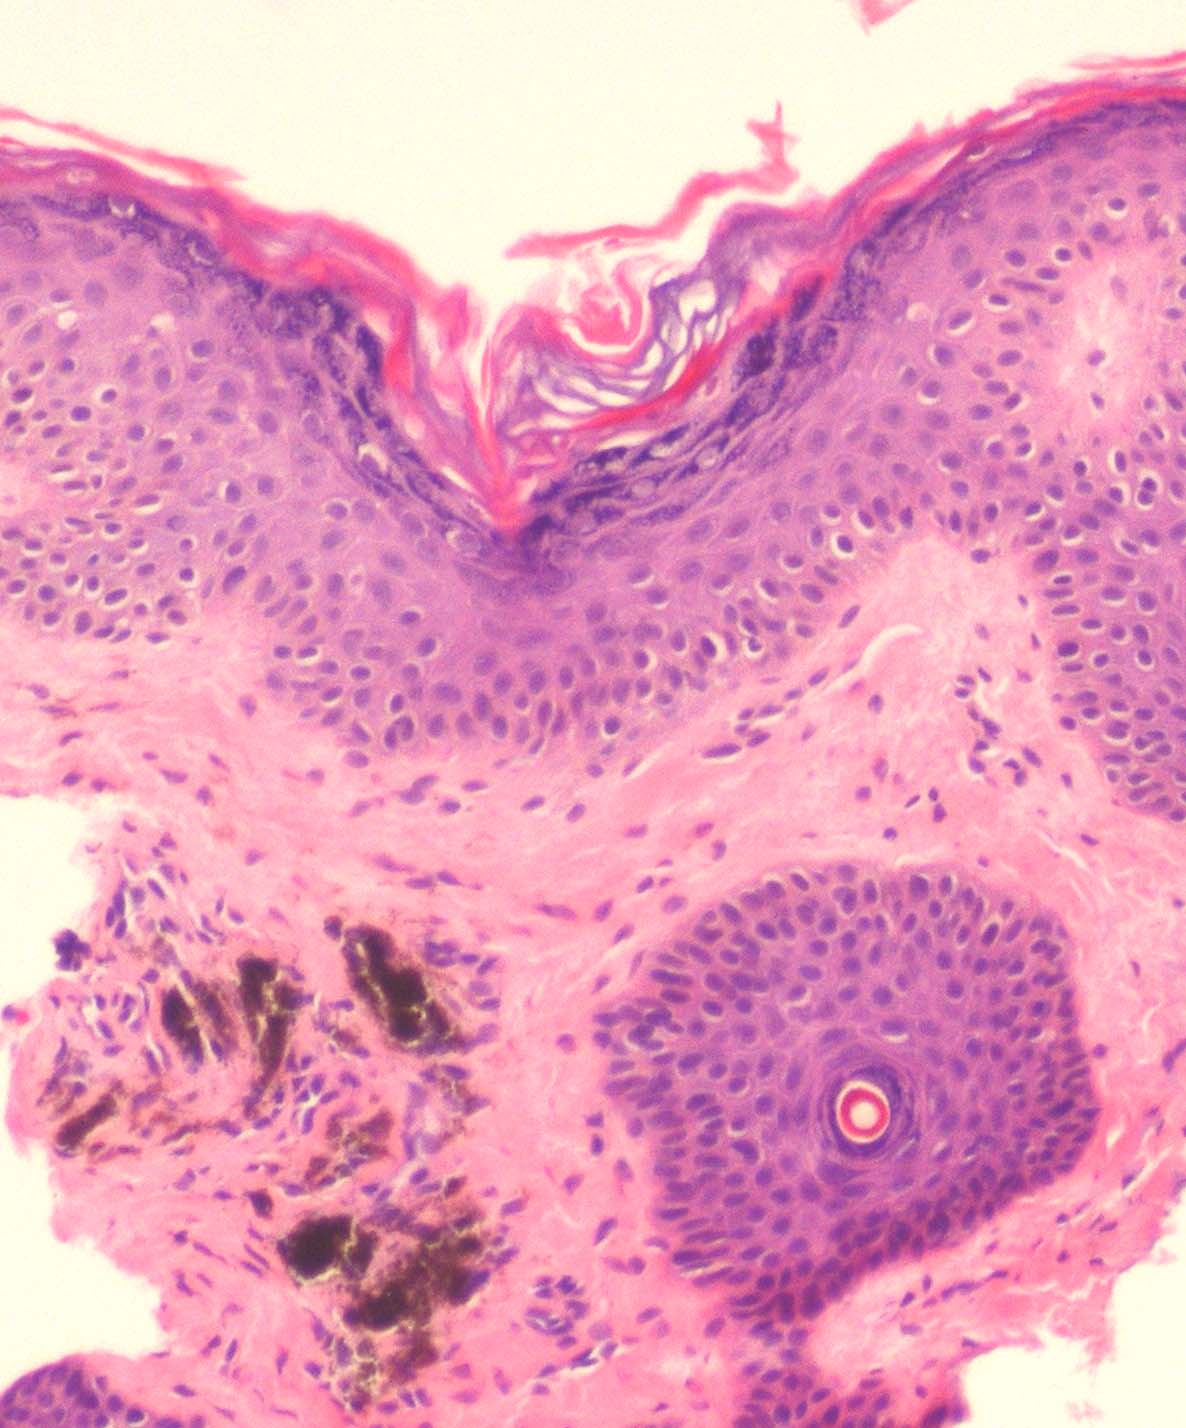

Atlas of skin histopathology

minocycline-pigmentation